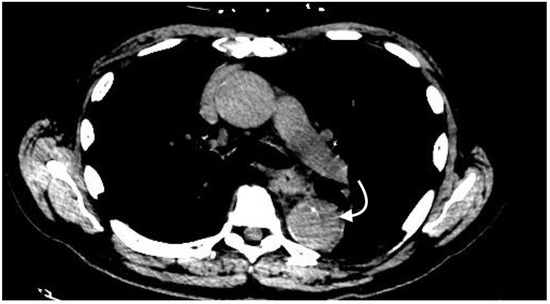

2.4.4. Intramural Hematoma